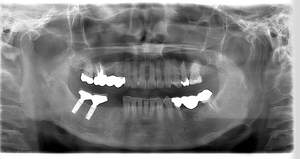

インプラント治療の症例4

レントゲン写真

- Befor

- After

| 治療内容 | 左下6番抜歯、左下6番7番骨造成、インプラント埋入 |

| 治療方針 | 元々支台歯に負荷がかかりやすいとされている延長ブリッジを抜歯し、1本単体でしっかりかめるようにインプラントを2本埋入した。骨吸収も進んでいたため、※GBR法で骨造成を同時に行った。 治療と並行して、全顎的な歯周病治療も行い、今後は歯周病が進行しないよう、こまめにメンテナンスに通っていただく。 |

| 担当者所見 | 6番は歯根分割された被せ物が7番の欠損部との延長ブリッジとされており、強い咬合と歯周病も相まって負荷がかかり動揺し、歯として機能しなくなったため、抜歯となった。 |